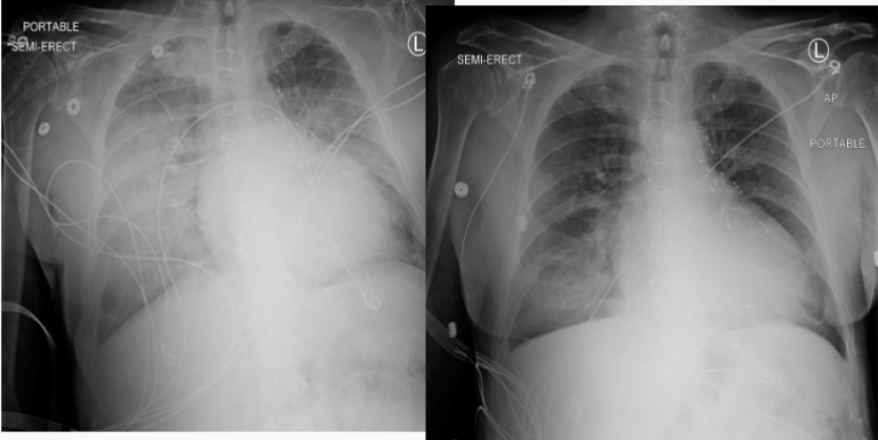

What was the patient’s original dx (left) and what caused improvement (right)?

Pulmonary edema- before (left) and after lasix aka “fluid pill” (right)